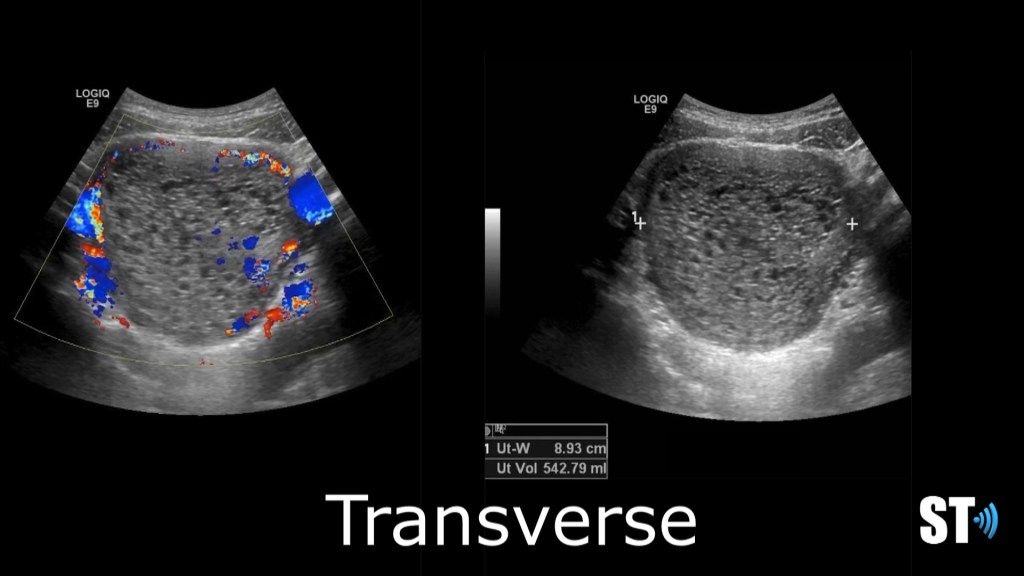

Complete mole transverse and sagittal images showing an enlarged, round uterus with a complex multi cystic endometrial complex. Hcg was 25,344